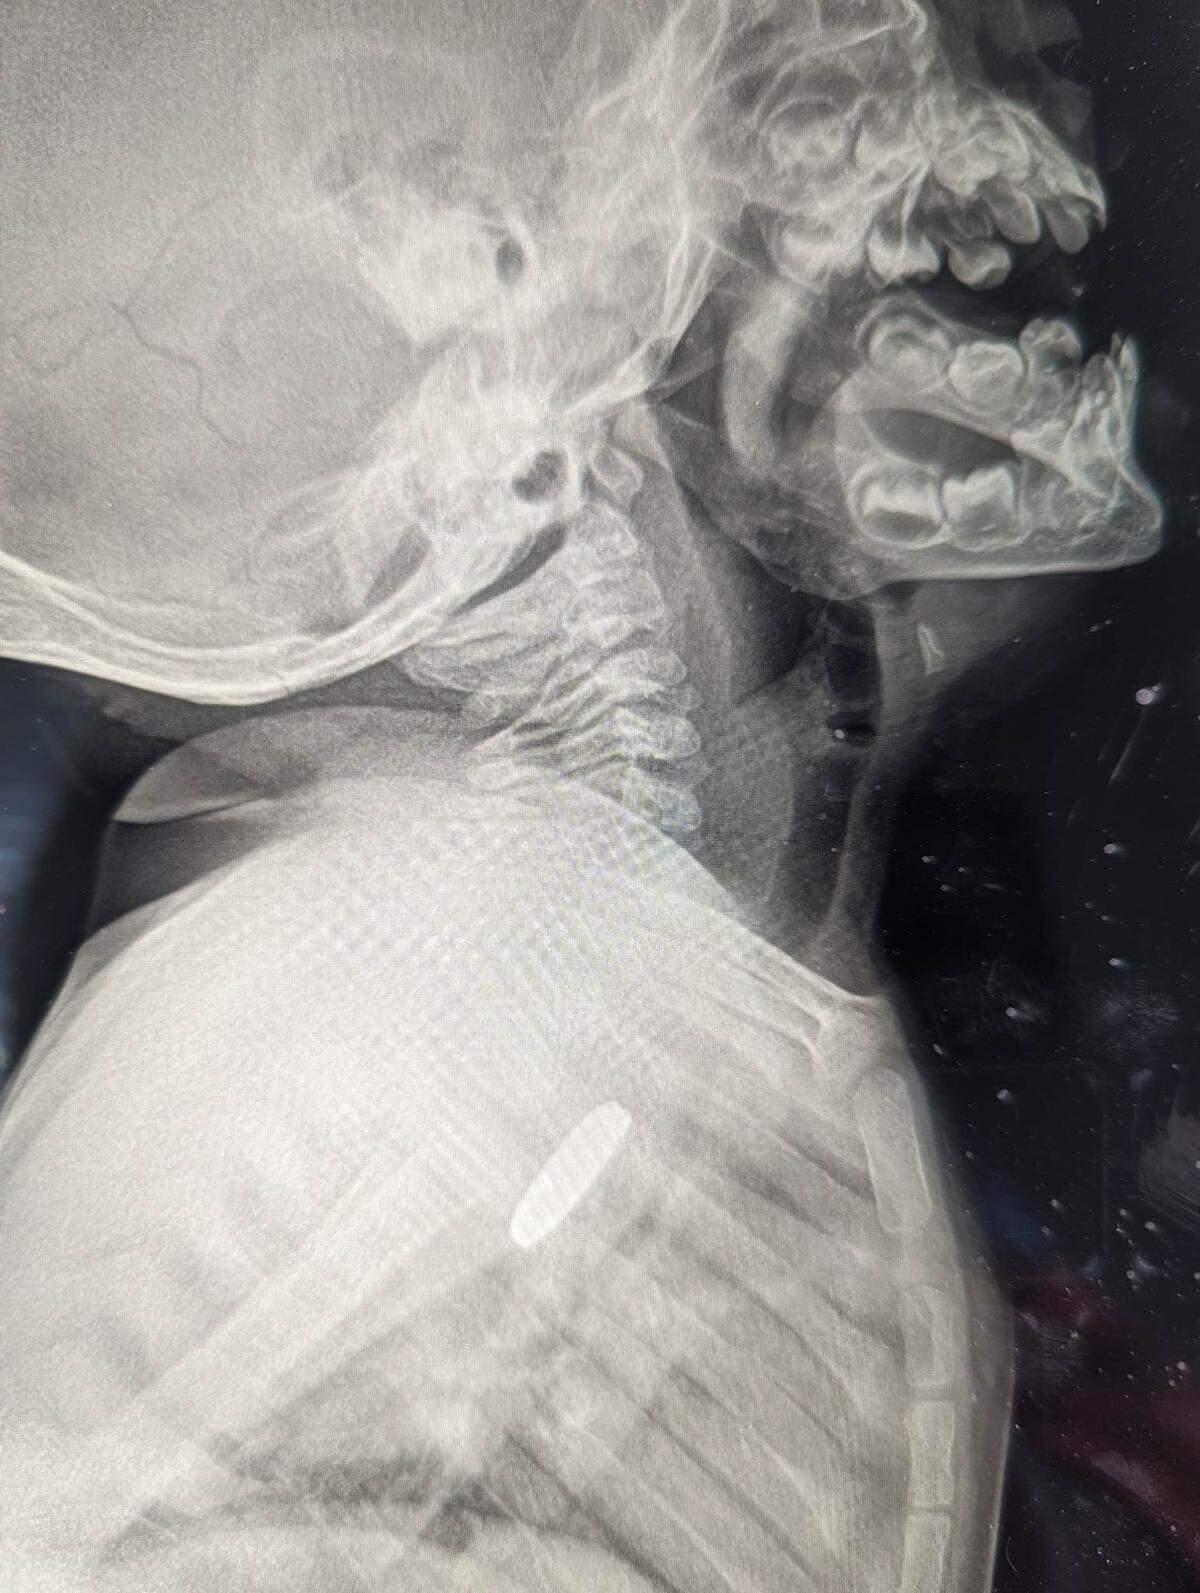

She took Luke to a different pediatrician, and this doctor ordered X-rays to take a look inside.

After a surgeon was called in to take a look, Erica McMillan said they told her there was something silver down there, but it was so stuck it would be dangerous to try to pull it out without a full team, in case something went wrong.

The surgeon told them they had found a lithium battery stuck to the inside of Luke’s esophagus, but it was wrapped in electrical tape, something that likely saved his life.

The battery had sat in Luke’s throat for five weeks by the time it was removed, so while it didn’t kill him, it still damaged the esophageal tissue. The next steps are to try to put that tissue back together.